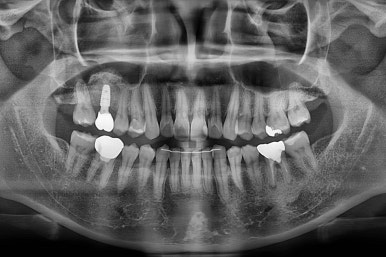

진행상황을 X-ray로도 확인해 줍니다.

아랫니 부분교정이 끝났고요.

어금니도 원위치로 많이 갔네요.

아랫니 부분교정과 어금니 부분교정은 비교적 조기에 끝났으나(7개월) 임플란트가 생각보다 오래 걸렸습니다.

적절한 공간 확보 이후 해당 부분의 뼈가 너무 얇아 임플란트를 하기에 부적절했던거죠.

상악동 거상술 + 골이식을 광범위하게 꽤 많은 양을 하고, 한참을 기다립니다.

이후에 적절한 시기에 임플란트 식립을 하고 보철을 하고 마무리를 합니다.